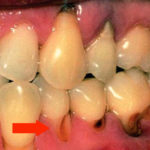

Кариес корня зуба фото

Кариес на корне зуба визуально практически никогда не определяется. Очень редко, и лишь в случаях, когда зубной камень значительно опустил ткани десны, может быть видно темное пятно или изъязвленный участок эмали. Чаще всего кариесом развивается на корнях передних нижних зубов и в межзубном промежутке. Во втором случае можно заметить снижение высоты десневого сосочка и увеличение межзубного промежутка в самой нижней его части.